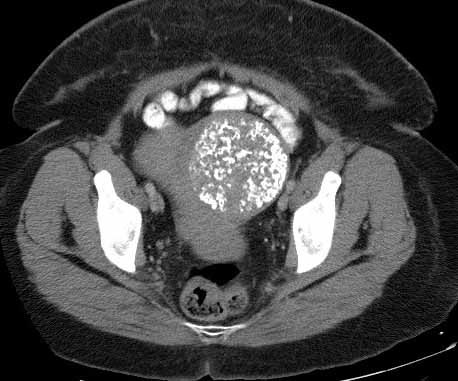

What is wrong with this pt?

Calcified uterine leiomyoma –amorphous calcification visible in the pelvis. This type of calcification suggests formation in a solid organ or tumor.